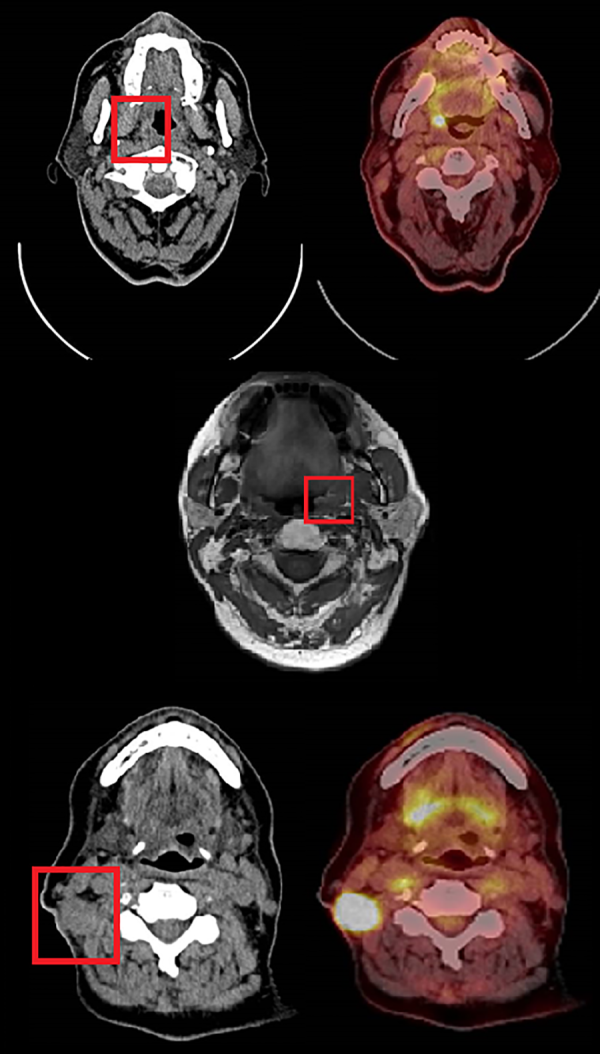

Patient 3 is a 63-year-old woman who was treated with induction chemotherapy followed by radical chemoradiotherapy for a T4N2bM0 tonsillar SCC. 4 months posttreatment a PET CT scan revealed metabolically active lesions within the right tonsil, glossotonsillar sulcus, and several right-sided neck lymph nodes. Patient demographic data is summarized in Table 1 and preoperative imaging is displayed in Figure 1.

Figure 1

Summary of patient preoperative imaging. TOP (Patient 1). Left-axial view contrast enhanced CT showing lesion within right tonsil suggestive of residual disease (red box). Right-axial PET CT showing a strongly FDG avidity within the same tonsillar lesion. MIDDLE (Patient 2). T1 axial view MRI demonstrating a 2-cm mucosal irregularity with increased enhancement in the left tonsillar fossa (red box). BOTTOM (Patient 3). Left-axial view contrast enhanced CT showing malignant appearing changes in right tonsil and glossotonsillar sulcus and an enlarged abnormal right neck node (red box). Right-axial view PET CT showing intense FDG uptake within enlarged right neck lymph nodes. FDG indicates fluorodeoxyglucose; MRI, magnetic resonance imaging; PET-CT, positron emission tomography-computed tomography.